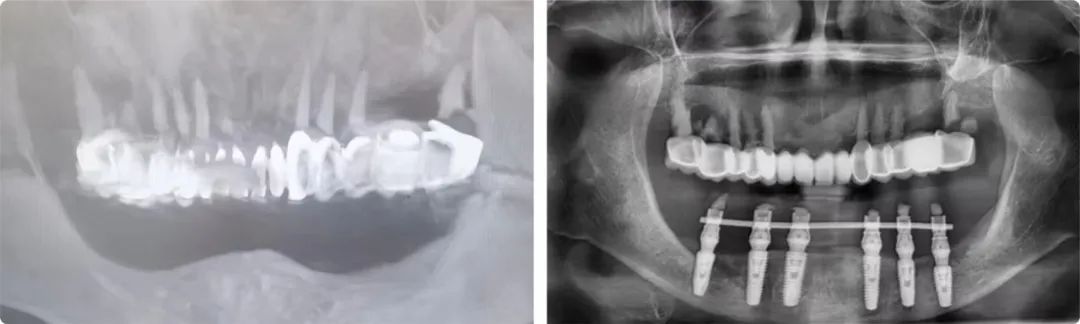

“患者牙槽骨的垂直高度太低,牙槽嵴高度不足9毫米,直接種植會傷及神經,首選方案是先做骨增量手術再種植,但她的情況根本做不了骨增量,只能選擇高風險的第二方案:先行雙側下頜神經游離術,通過手術把左右兩側的下頜神經撥到安全位置,再做種植。”

患者術前術后檢查報告

老人和家屬非常信任姜辰,接受了這個方案。術中植入了6枚植體,術后即刻修復完成戴牙,老人的咀嚼功能當天恢復。